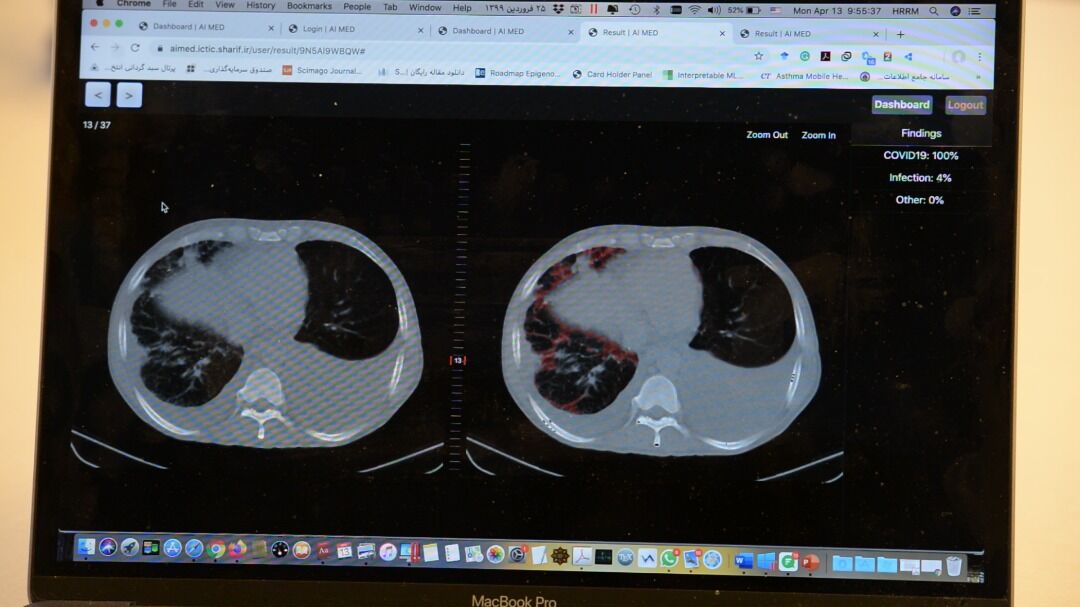

وی بیان کرد: کشور چین از هوش مصنوعی برای تشخیص این بیماری استفاده کرده است و یک شرکت برخاسته از دانشگاه استفورد آمریکا نیز فعالیت‌هایی را در این زمینه انجام داده است، ما نیز با تمرکز بر کاربرد هوش مصنوعی در سی تی اسکن، با نوآوری سامانه ای را برای تشخیص سریع و با دقت کووید ۱۹ طراحی کرده ایم که قابلیت تخمین حجم ناحیه عفونی را نیز دارد.

رییس گروه علم و فناوری اطلاعات و ارتباطات جایزه مصطفی(ص) همچنین افزود: سیستم‌هایی که در کشور چین یا آمریکا استفاده می‌شود، دقت بالای ۹۰ درصد دارند، نبوغ جوانان دانشمند ما، با پیش پردازش نوآورانه بر روی تصاویر سی‌تی اسکن و استفاده از راهکارهای توصیف پذیری در یادگیری ماشین، سامانه ای با دقت و حساسیت بالاتری را به وجود آورده است.

ربیعی گفت: سامانه ای که این تیم تحقیقاتی براساس هوش مصنوعی طراحی کرده است با نوآوری در پیش پردازش و پردازش تصاویر در شبکه‌های عمیق توصیف پذیر، به صورت پایدار و در زمانی کمتر از یک دقیقه، نتایج خوب و با دقت و حساسیت بالای ۹۷ درصد را به دست آورد. علاوه بر این سامانه حجم نواحی عفونی را نیز محاسبه می کند. این سامانه به طور رایگان در اختیار پزشکان و مراکز درمانی جهان قرار می‌گیرد تا با توجه به تعداد زیاد بیماران بتواند به پزشکان در تشخیص سریع و با دقت این بیماری کمک کند.

وی با بیان اینکه کوید ۱۹ در برخی از تصاویر در مراحل اولیه بیماری با چشم غیرقابل مشاهده است، اظهار کرد: از بیمارستان‌های مختلف، نمونه‌هایی را داشته‌ایم که امکان تشخیص این بیماری برای آن­ها از مشاهده تصاویر وجود نداشته است، اما سامانه هوشمند آی مد باتوجه به طراحی مناسب آن توانسته بیماری را در مراحل اولیه تشخیص دهد.